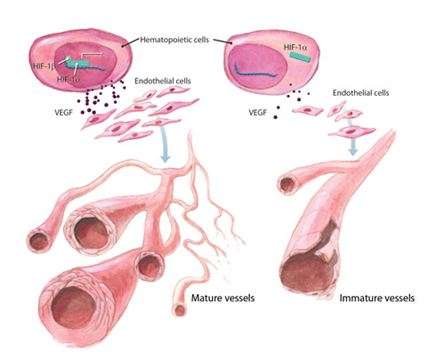

Uno de los genes diana que en los procesos de hipoxia es el gen del VEGF. Este factor, como su nombre indica, provoca la formación de nuevos vasos sanguíneos y capilares (proceso conocido como angiogénesis) y aumenta la descarga de oxigeno a los tejidos (Carmeliet, 2005).

En los procesos cancerigenos se produce este fenómeno en mayor medida, ya que en el crecimiento de la masa tumoral es necesaria la aparición de nuevos vasos sanguíneos. Por este motivo, se piensa que la inhibición en la primera instancia del VEGF puede provocar en definitiva la parada de la angiogénesis como posible terapia anticancerígena (Ferrara, 2005).

Otros estudios demuestran que la combinación de quimioterapia e inhibidores de la angiogénesis mejora el tratamiento tumoral y aumento de la supervivencia en las enfermedades (Ferrara y Kerbel, 2005). No obstante todas estas iniciativas, encaran que falta mucho para estudiar acerca de este mecanismo en ciertas patologías, ya que no se informa de forma adecuada acerca de: la dosis, duración del tratamiento, monitoreo del tratamiento entre otros factores importantes para buscar un tratamiento óptimo.

Por otra parte, en el sentido opuesto, hay otros estudios que dicen que la angiogénesis puede solucionar totalmente o parcialmente, posibles isquemias, infartos o otras patologías que desencadenan o provocan una mala perfusión, y así con el factor endotelial se podría conseguir que estas zonas con mala perfusión estuvieran mejor irrigadas. Esta situación en la rehabilitación cardiaca resulta muy interesante y es más se ha observado que los estímulos de hipoxia intermitente pueden ayudar en la rehabilitación cardiaca.

Figura 2. VEGF inducido por el factor HIF. Acción sobre las células endoteliales (www.rndsystems.com/DAM_public/5940.jpg).